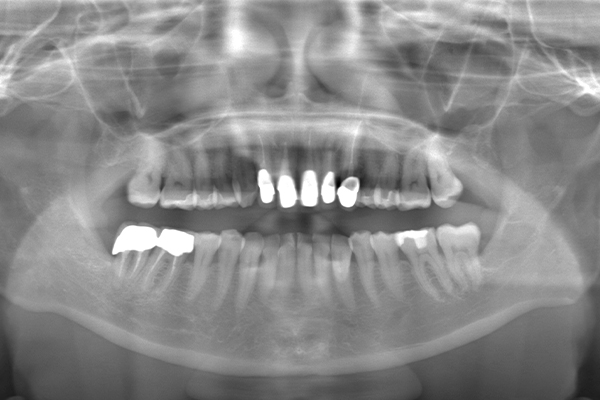

Case.02

インプラントの症例 インプラントの症例

治療前〜治療後のレントゲン写真

患者様の要望奥歯にインプラント治療したい

治療期間4ヶ月

治療費用880,000円

治療内容左上奥歯に2本インプラント埋入

治療のリスクネジが緩む可能性あり